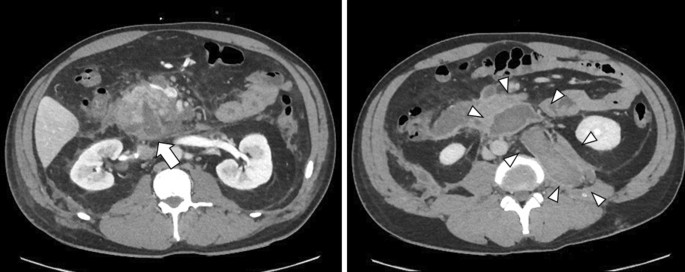

On day 5, although ERCP was performed, the scope did not reach Vater’s papilla due to the narrow cavity of the decompressed duodenum. The serum amylase level gradually decreased and then normalized. On day 12, CT revealed a wedge-shaped, low-density area in the pancreatic head, and consecutive pseudocysts behind the pancreas and in the left psoas muscle (Fig. 3). Thereafter, a percutaneous drain was placed through the stab wound, behind the pancreatic head. On day 22, contrast radiography through the percutaneous drain revealed the proximal and distal parts of the main pancreatic duct (Fig. 4); therefore, the patient was diagnosed with AAST grade IV pancreatic injury. On day 26, an endoscopic nasopancreatic drainage (ENPD) tube was inserted across the disruption (Fig. 5), and on day 38, CECT showed a marked reduction in the fluid collection (Fig. 6). The ENPD tube was changed to an endoscopic retrograde pancreatic drainage (ERPD) tube on day 40, and he was discharged on day 61. The ERPD tube was removed 10 months later, and stenosis has not been confirmed on magnetic resonance cholangiopancreatography after 1.5 years.